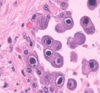

The histological sample below is indicavtive of what infection?

CMV

The histological slide shows Owl’s eye inclusions, which are indicative of CMV-infected cells.

CMV has what characteristic histological appearence?

Owl’s eyes nuclear inclusions

Remember: you “C” with your eyes, so CMV is indicated by owl’s eyes

Owl’s eyes are inclusion bodies surrounded by a halo in CMV infected cells.